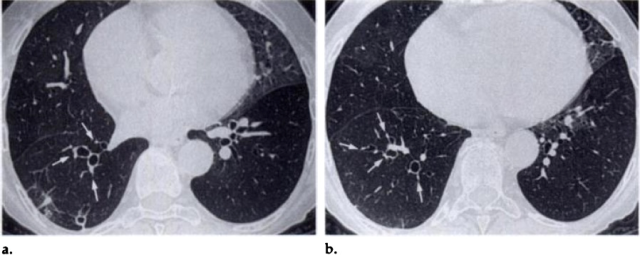

慢性肺血栓栓塞是肺动脉血流减少的一种常见原因。以下是一例50岁非吸烟者的胸部CT图像,患者既往有双侧大面积急性肺栓塞病史,3年后转为慢性肺栓塞。薄层CT吸气相可见右肺叶各支气管分支有圆柱状扩张伴微小动脉影,呈现与印戒征相似的影像学表现(箭头),舌部存在马赛克征[8]。

50岁慢性肺血栓栓塞患者的胸部CT:印戒征样影像学表现[8]